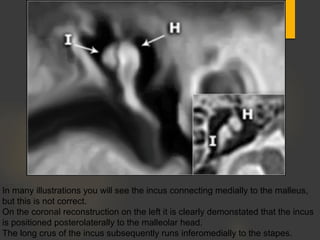

In many illustrations you will see the incus connecting medially to the malleus,

but this is not correct.

On the coronal reconstruction on the left it is clearly demonstated that the incus

is positioned posterolaterally to the malleolar head.

The long crus of the incus subsequently runs inferomedially to the stapes.